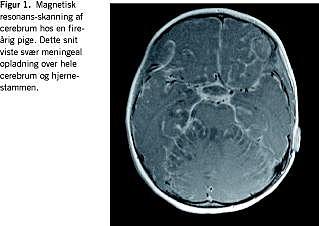

Pigens symptomer blev forværret i fireårsalderen. Hun mistede motoriske og sproglige færdigheder og fik anfaldsfænomener, koncentrationsbesvær, skelen, dysartri, ataksi, faldtendens, ufrivillige vandladninger og vægttab. En CT af cerebrum viste et slankt ventrikelsystem, hvilket var foreneligt med fuld regression af hydrocefalus. En MR-skanning af cerebrum viste betydelig meningeal opladning (Figur 1 ). Hiv, neurosyfilis, sarkoidose og tuberkulose blev udelukket. Et elektroencefalogram viste normale forhold. Spinalprotein udtaget ved lumbalpunktur var igen > 6,0 g/l. En MR-skanning af columna totalis viste en intramedullær tumor, der strakte sig fra Th3 til Th9 med karcinomatøs udsæd.